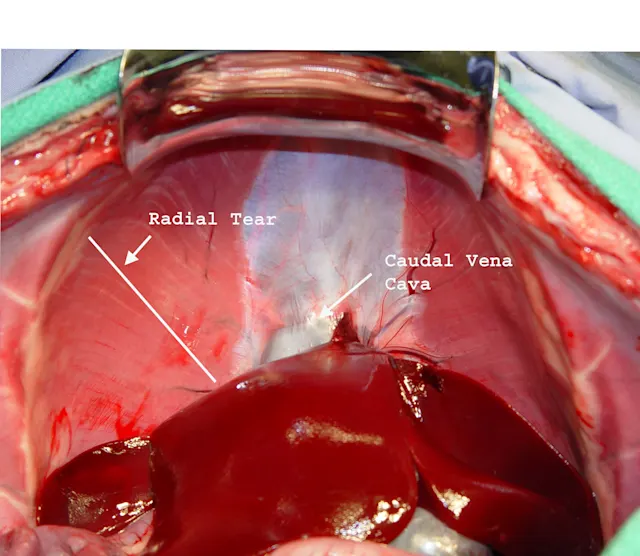

If resistance is felt during reduction of organs, the hernia can be enlarged as shown in the photograph. The incision made to enlarge the hernia should also facilitate and simplify closure (i.e., enlarge the hernia ventrally and away from any transdiaphragmatic structures). Take care not to damage the caudal vena cava, esophagus, or aorta and structures on the thoracic side of the diaphragm when enlarging the hernia.